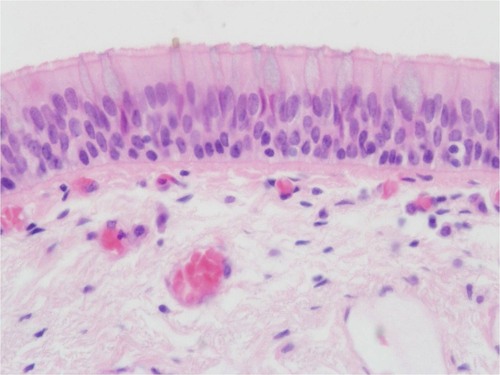

pseudostratified columnar

appears layerd but consist of cells all attached to a basement membrane; commonly have cilia and goblet cells found in respiratory tract